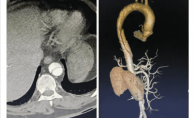

浙江大学医学院附属第一医院、阿里巴巴达摩院发布了全球首款用于胸痛急诊场景的AI模型“iAorta”,可用常规平扫CT在几秒内识别急性主动脉综合征,将确诊时间缩短至2小时内。 实际应用中,iAorta从1万多名胸痛患者中精准发现了21例,并及时救治。 主动脉是人体最重要的血管,其夹层、壁间血肿、穿透性溃疡等结构性病变被称为急性主动脉综合征(AAS),属于危急的心血管疾病,起病隐匿、进展迅速,但难以第一时间确诊,24小时内若不能确诊并处理,死亡率可达30%。AAS的临床症状常与心肌梗死、胃肠炎等疾病相似,容易混淆,而且常规检查手段识别率较低,导致误诊、漏诊和延迟诊断的情况时有发生。浙大一院与达摩院等机构组建了联合研究团队,首创“平扫CT+AI”识别急性主动脉综合征,帮助医生早期确诊。 达摩院团队基于在“平扫CT+A